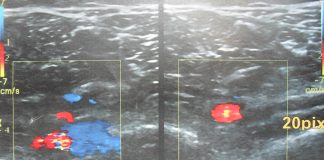

Tromboza venoasa profunda

Tromboza venoasa profunda este o afectiune grava care afecteaza starea de sanatate a venelor, prin ea se intelege blocarea partiala sau completa a vaselor...